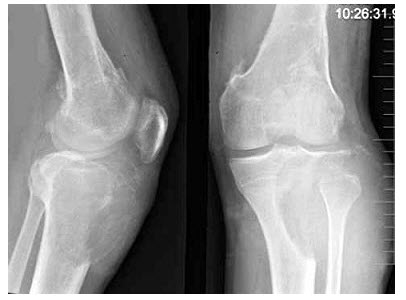

女,30岁,右膝关节酸胀,疼痛不适5月,X线检查如图所示,下列描述正确的是()

A.骨质呈膨胀性破坏

B.骨质呈肥皂泡样破坏

C.骨质呈横向偏心性破坏

D.以上均正确

E.以上均不正确